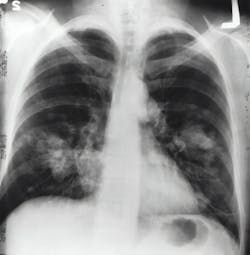

Assay identifies patients with non small-cell lung cancer eligible for specialized therapy

The U.S. Food and Drug Administration (FDA) has approved the use of the Roche's VENTANA PD-L1 (SP263) Assay in non-small cell lung cancer (NSCLC) as a companion diagnostic test for Tecentriq, according to a news release from Roche.

Tecentriq received FDA approval as adjuvant treatment following surgery and platinum-based chemotherapy for adults whose Stage II-IIIA NSCLC tumors have PD-L1 expression on at least 1% of tumor cells. The VENTANA PD-L1 (SP263) Assay identifies NSCLC patients who may be eligible for Tecentriq (atezolizumab) monotherapy in this indication.